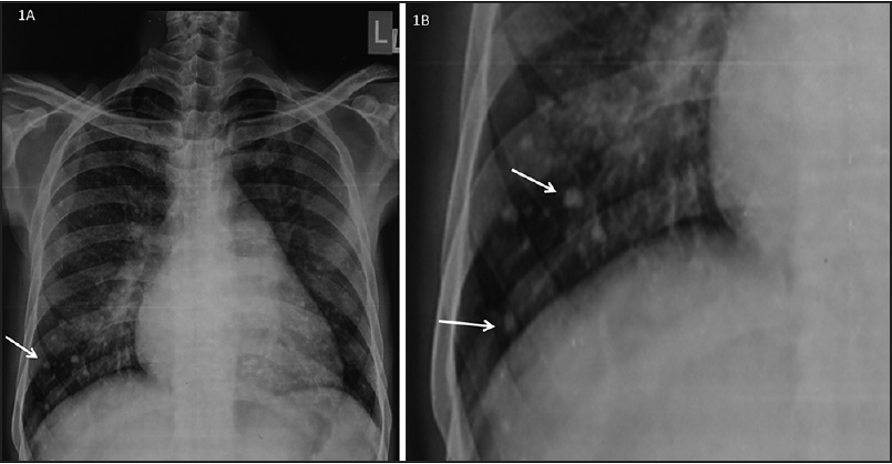

CXR Z

• Left atrial enlargement

• Mitralisation of heart: straightening of left heart border

• Elevation of left mainstem bronchus

• Evidence of mitral calcification

• Evidence of pulmonary edema kerley’s b lines

• Double contour of the right border of heart

Imaging

PA view: ⇒ Left atrial enlargement:

• Convexity or straightening of the left atrial appendage.

• Left heart border is straight or convex

• Double density of RT  cardiac border

• Elevation of the left main bronchus and splaying of the carina